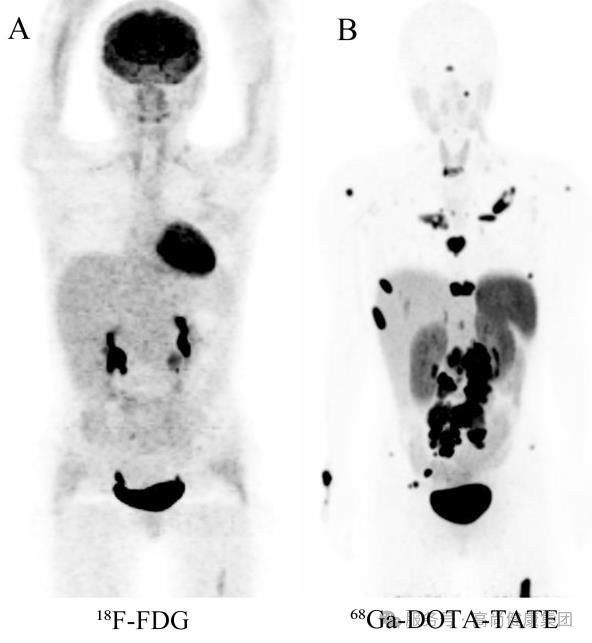

18F-FDG PET(图 A)未见明显高代谢病变;

68 Ga-DOTA-TATE PET(图 B)示双肺、肝脏、淋巴结及骨骼多发阳性病灶,诊断为神经内分泌瘤多发转移,为患者进行了准确的分期。[2]